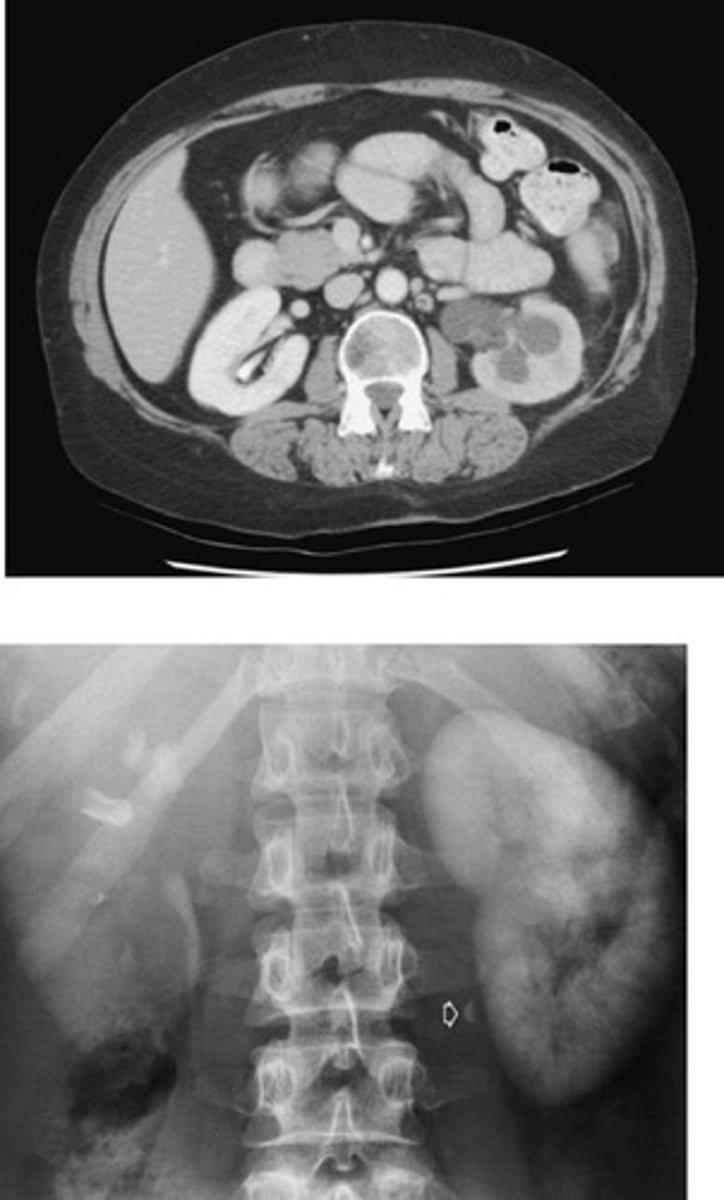

Hydronephrosis

What is the condition where one or both kidneys become stretched and swollen as the result of a build-up of urine inside them?

- Renal Cyst

- U/S and CT

- What are fluid filled sacs that forms on/in the kindey, displaces the calyces as it grows, may be single/multiple, and vary in size?

- What imaging modalities are used to diagnose this pathology?

- Polycystic Renal Disease

- "Swiss Cheese"

- What is the inherited disorder in which multiple cysts cause lobulated kidney enlargements and renal impairment?

- How does this disorder appear radiographically?